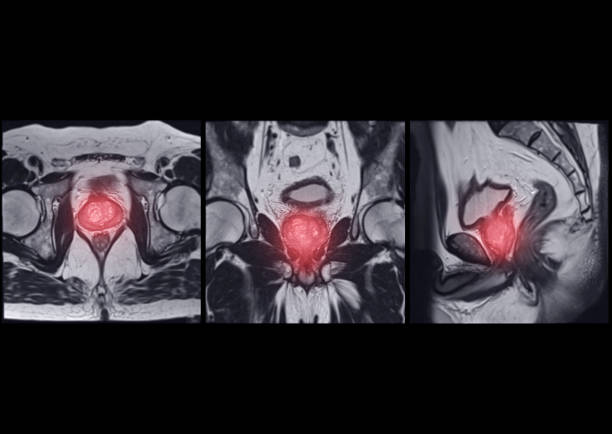

방광암은 방광 내부에 악성 종양이 생긴 것을 말합니다. 이 종양은 방광 벽에서 시작하여 방광 내부로 침입할 수 있으며, 심각한 경우 다른 조직이나 기관에도 전이될 수 있습니다.

방광암은 초기 증상이 미미하게 나타나기 때문에, 정기적인 건강 검진을 받는 것이 중요합니다. 방광암의 조기 발견을 위해 소변검사, 방광 내시경검사 등의 검사를 시행할 수 있습니다. 이를 통해 환자의 건강 상태를 파악하고, 조기 발견 및 치료로 환자의 생존율을 높일 수 있습니다.